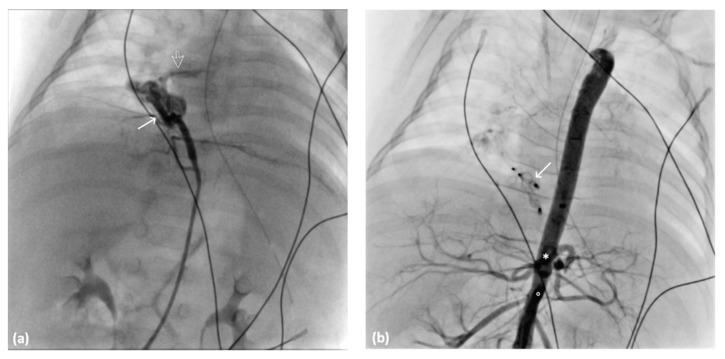

Herein, we describe an aberrant artery to a normal lung, focusing on its classification, embryological hypotheses, diagnostic methods, and treatment modalities. We present three cases of aberrant arterial supply to a normal lung in various age groups (51 years, 5 months, and 29 years). The cases presented symptoms ranging from hemoptysis to respiratory distress. Successful transarterial embolization was performed in the 5-month-old infant. In addition, we collected case reports published from 1962 to the present from the literature to compare the trends in management and variations in manifestations.

在此,我们描述了一条通向正常肺的异常动脉,重点关注其分类、胚胎学假说、诊断方法和治疗方式。我们呈现了三例不同年龄组(51岁、5个月和29岁)通向正常肺的异常动脉供血病例。这些病例出现了从咯血到呼吸窘迫等不同症状。对5个月大的婴儿成功实施了经动脉栓塞术。此外,我们从文献中收集了1962年至今发表的病例报告,以比较管理趋势和表现差异。